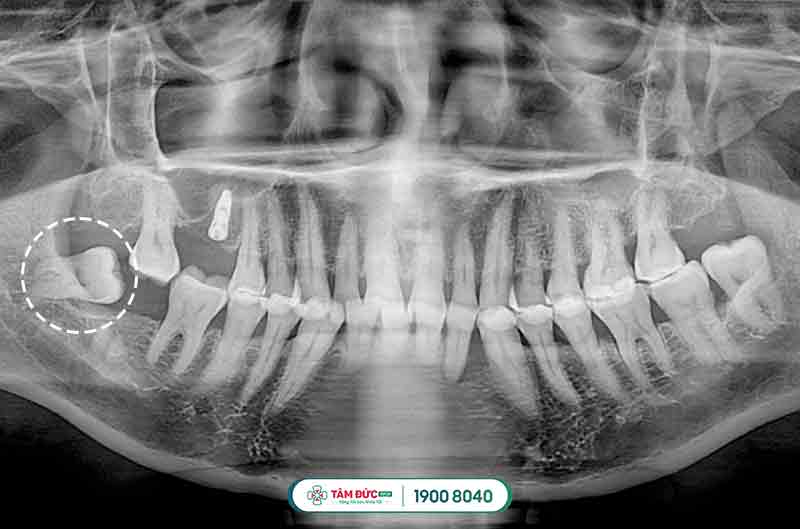

Răng khôn mọc lệch và bị sâu

Đối với các trường hợp mọc răng khôn bị thiếu chỗ vì lúc này xương hàm đã ngừng tăng trưởng và phát triển, chịu tác động bởi quá trình ăn uống hàng ngày, khiến răng khôn bị mọc ngầm dưới nướu, mọc lệch đâm vào má, vào răng bên cạnh gây nên tình trạng đau răng khôn dữ dội, khó chịu và ảnh hưởng đến cấu trúc hàm mặt, sức khỏe răng miệng.

Răng khôn mọc lệch gây đau

Răng khôn mọc lệch đâm vào răng kế cận

Răng khôn mọc ngầm thường có hiểu hiện làm nướu sưng tấy, viêm đỏ, khó há miệng. Vì xương hàm không có đủ vị trí nên nó sẽ đâm sang răng bên cạnh, nó sẽ làm chiếc răng khỏe mạnh kế bên dần bị tiêu hủy, lung lay có thể dẫn đến sâu, nặng hơn nó sẽ khiến chiếc răng này bị xô đẩy chèn ép và rụng đi gây mất răng. Răng khôn mọc lệch, ngầm thường gây ra những cơn đau răng khôn âm ỉ kéo dài trong khoản 2 tới 3 ngày.